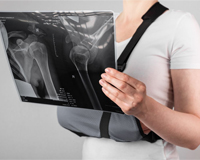

Imágenes diagnósticas con rayos X en Guatemala

Equipos de última generación

Evaluación detallada

Facilita decisiones acertadas